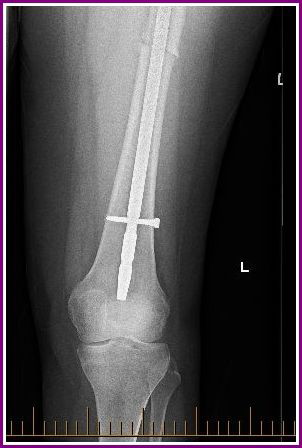

Today was my much anticipated appointment with my Orthopaedic Surgeon and it went pretty much as I expected really. My leg is still broken and it is showing minimal signs of healing but all to be expected due to the nature of the break.

He wants to see me again in 3 months, with further x rays, (not 6 months as expected) as he is a little concerned that the screw above the knee ( called the dynamic screw) may have to be removed. I literally dodged a bullet today in regards to having that kind of surgery as he could see that the screw still has some capability to move…a good thing apparently.